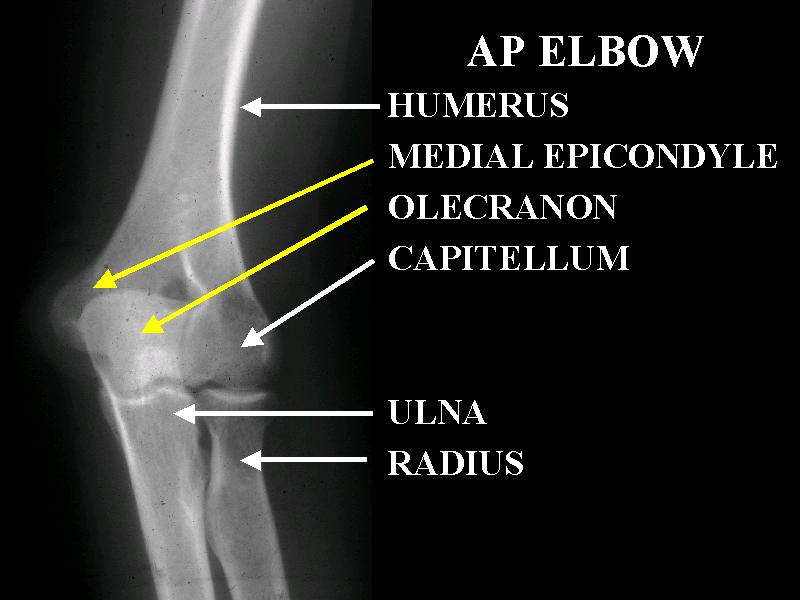

MS 28 AP ELBOW